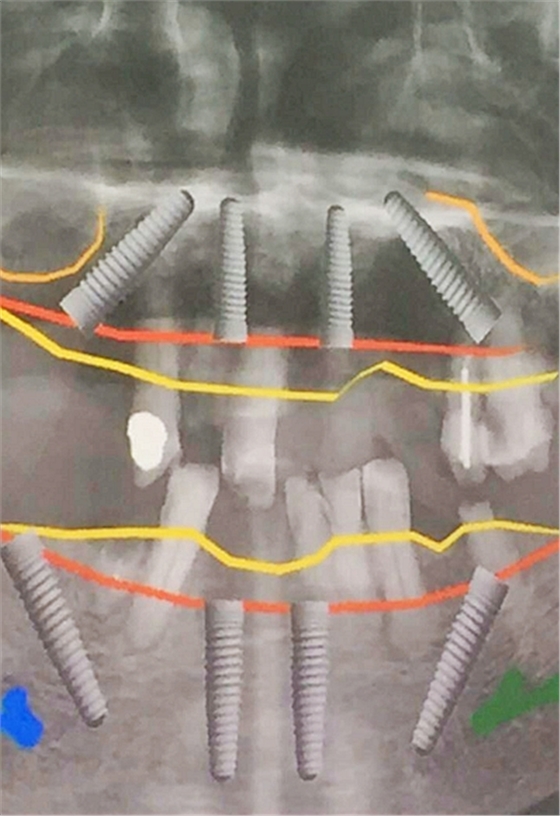

毛國斌種植病例——群討論分享